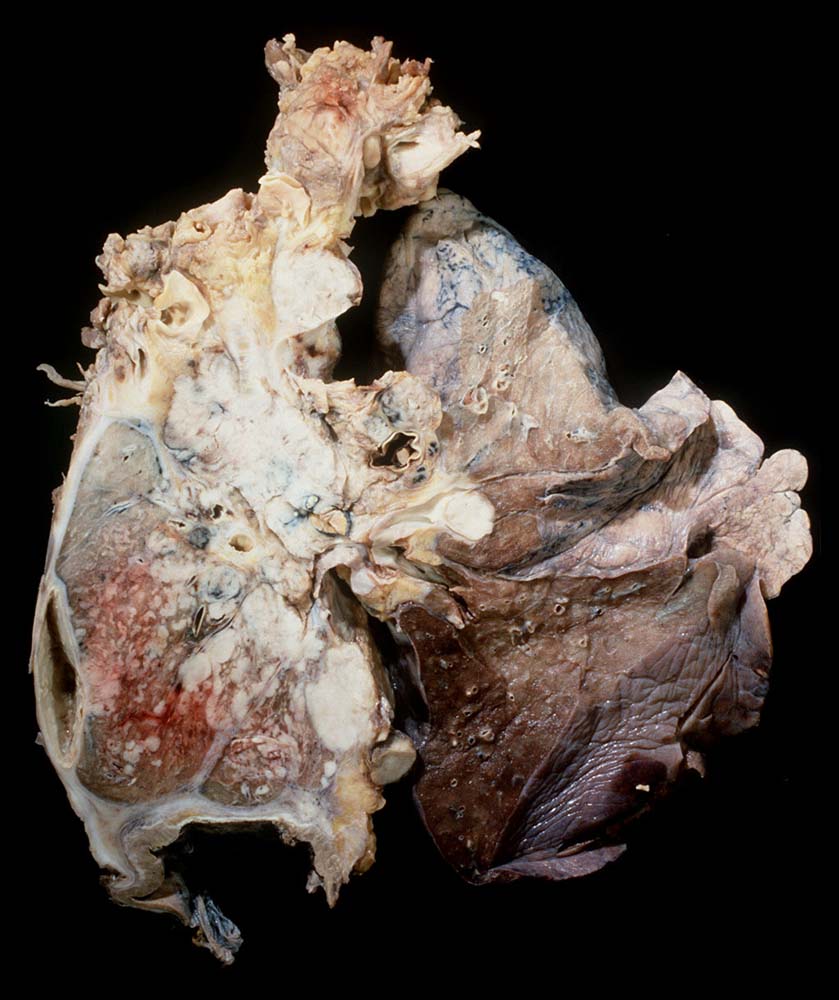

Kleinzellige Karzinome entwickeln sich bevorzugt zentral.

Pathologischer Befund